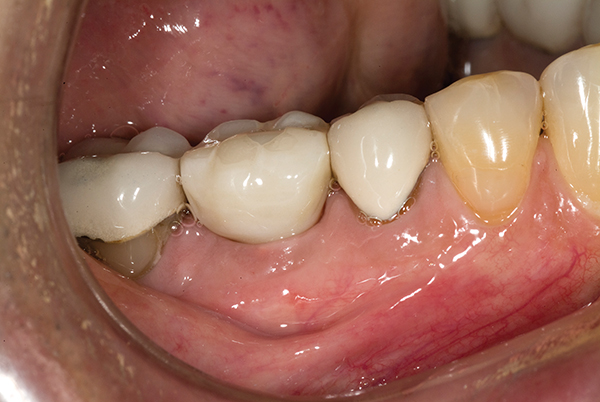

A mandibular right first molar was extracted due to an advanced Class III furcation and an irreversible pulpitis—a combination lesion. An immediate implant placement protocol was elected, and a PEEK abutment was placed on the implant (Figure 1). After 3 months of healing, a scan body was placed on the osseointegrated implant (Figure 2 and Figure 3), and an intraoral scan was taken (TRIOS Pod) (Figure 4) for the fabrication of a screw-retained crown.

Fig 2. Examples of intraoral scan bodies for various implant platforms. Scan body on far right was used in this case for 5.5-mm conical-connection/platform-switch implant.

Figure 2